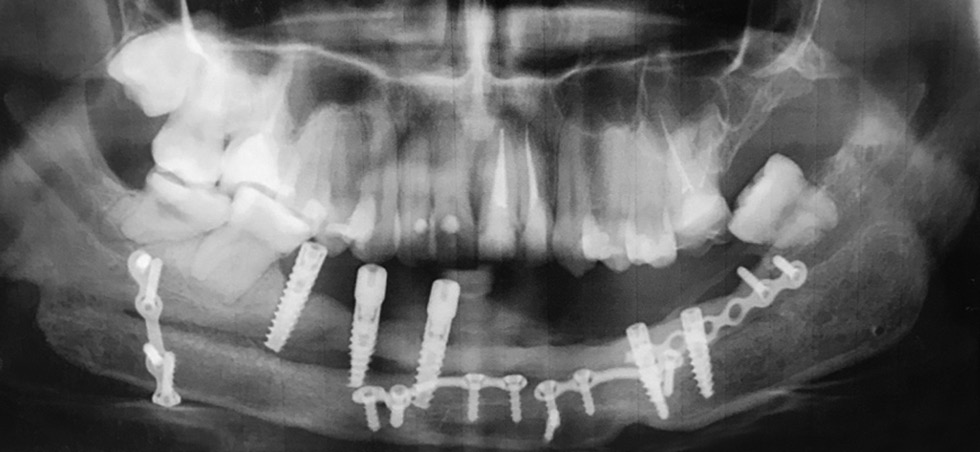

At age 10, the patient underwent local plastic correction of the auricles due to everted ears. At age 17, upon completion of the growth of the facial part of the skull, preparations were started for the final surgery, including the removal of the titanium endoprosthesis plate and its replacement with a vascularized bone graft. The surgical treatment was indicated, among other things, as the jaw growth was completed. A CT scan showed a pronounced discrepancy between the size of the base (titanium endoprosthesis) of the lower jaw and the size of the formed upper jaw and the skull as a whole. Further preservation of the endoprosthesis could lead to the dislocation of the jaw heads from the articular cavities (Fig. 4).

Fig. 4. Patient B (17 years old). Postoperative deformity of the lower jaw. Condition after the removal of the neoplasm and arthroplasty of the jaw with a titanium reconstructive plate: a, appearance and oral cavity; b, X-ray image